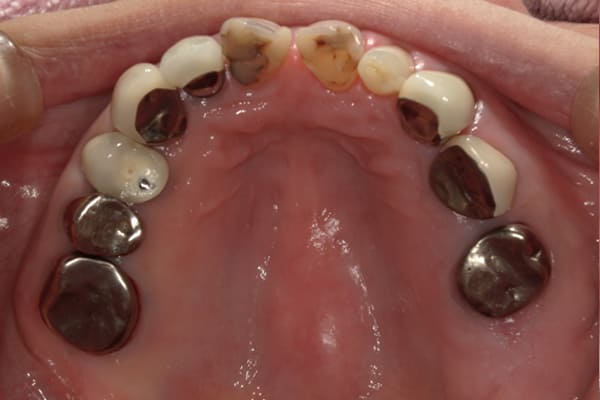

上顎治療前

-

上顎治療後

根のみの7本は虫歯にもなっており歯肉は腫れあがっています。

残りの歯もレントゲンで重度の歯周炎によりぐらぐらな状態でした。